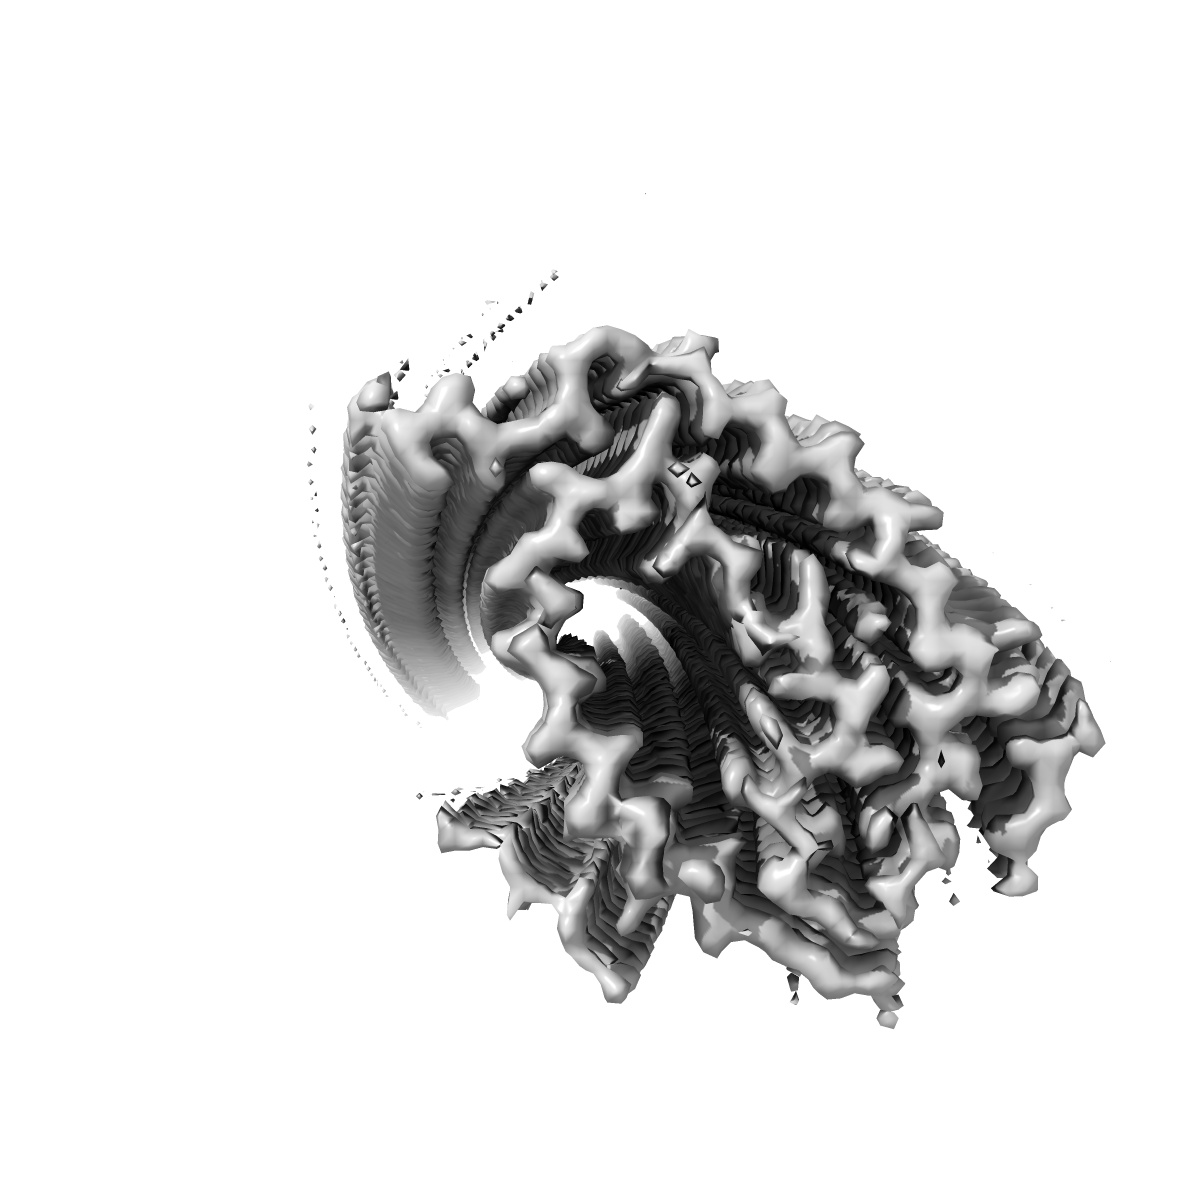

In vitro assembled 258-391 tau filaments, 700 rpm (38a)

EMD-14030

Helical reconstruction

2.44 Å

Sample Organism: Homo sapiens

Sample: Tau

Fitted models: 7qk3

Deposition Authors: Lovestam S, Scheres SHW

Assembly of recombinant tau into filaments identical to those of Alzheimer's disease and chronic traumatic encephalopathy.

Lovestam S, Koh FA, van Knippenberg B , Kotecha A , Murzin AG, Goedert M , Scheres SHW

(2022) eLife , 11

PUBMED: 35244536

DOI: doi:10.7554/eLife.76494